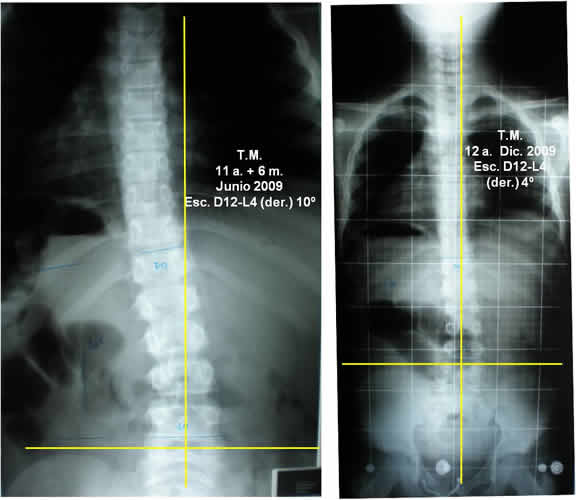

Escoliosis Lumbar

- Paciente: T.M. 11 años + 6 meses. Masculino.

- Motivo de consulta: Morfológico.

- Diagnóstico médico: Escoliosis lumbar.

- Inicio de tratamiento: Septiembre de 2009.

- Fin del tto.: Diciembre de 2009

- Total de sesiones realizadas: 11 sesiones, 1 vez por semana.